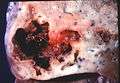

Lung abscess is a type of liquefactive necrosis of the lung tissue and formation of cavities (more than 2 cm)[1] containing necrotic debris or fluid caused by microbial infection.

This pus-filled cavity is often caused by aspiration, which may occur during anesthesia, sedation, or unconsciousness from injury. Alcoholism is the most common condition predisposing to lung abscesses.

Lung abscesses are often on one side and single involving posterior segments of the upper lobes and the apical segments of the lower lobes as these areas are gravity dependent when lying down. Presence of air-fluid levels implies rupture into the bronchial tree or rarely growth of gas forming organism.